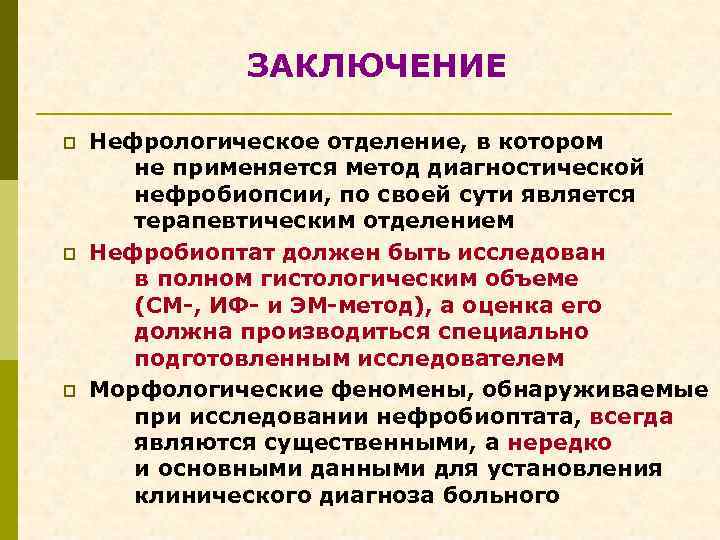

ЗАКЛЮЧЕНИЕ p p p Нефрологическое отделение, в котором не применяется метод диагностической нефробиопсии, по своей сути является терапевтическим отделением Нефробиоптат должен быть исследован в полном гистологическим объеме (СМ-, ИФ- и ЭМ-метод), а оценка его должна производиться специально подготовленным исследователем Морфологические феномены, обнаруживаемые при исследовании нефробиоптата, всегда являются существенными, а нередко и основными данными для установления клинического диагноза больного